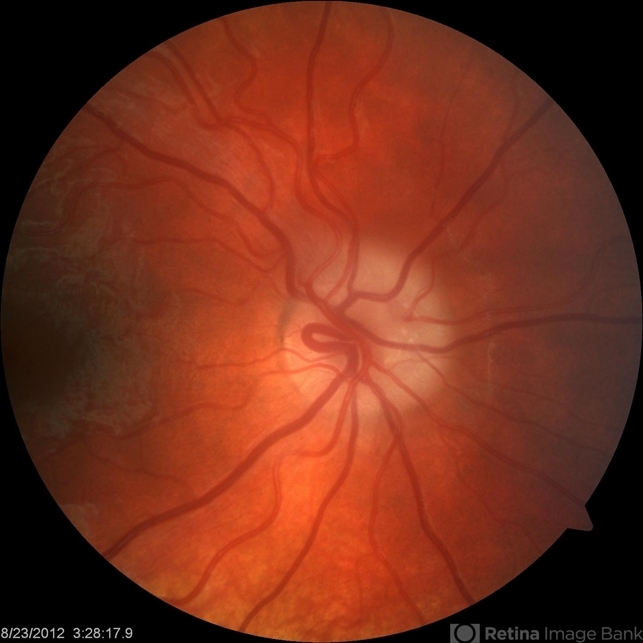

By John S. King, MD

Retina Associates, PA - Uploaded on Aug 24, 2012.

- Kristin Konecki, OcuSight Eye Care Center, Rochester, NY

- Imaging device

- Fundus camera